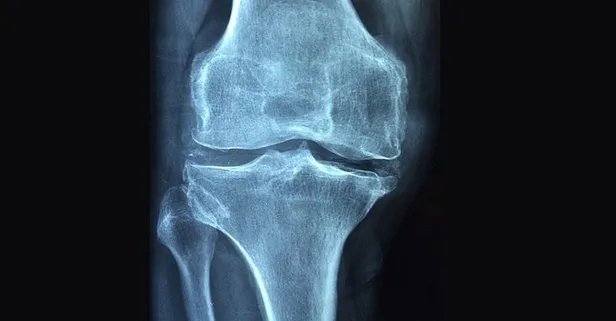

Sık görülen metabolik kemik hastalığı olan osteoporoz, kemik kütlesinin azalmasıyla ortaya çıkıyor. Tüm ırklarda, tüm yaş gruplarında ve her iki cinste de görülmekle birlikte, yaşlı beyaz kadınları da tehdit ediyor. Kemik kaybı ve osteoporoz riski yaşla birlikte artıyor. Kemik kaybı kadınlarda özellikle menopoz döneminde hızlandığından, kadınlar genellikle osteoporoz için daha yüksek risk grubunda yer alıyor. Osteoporoz genellikle 65-74 arasında kapıyı çalıyor. Kemik yoğunluğunun azalması kemiğin gücünün azalmasına yol açıyor. Hastalığın yol açtığı kırıklar, el bileği, omurga ve kalçada görülüyor. İşte bu nedenle hastalığın erken dönemde tespit ve tedavi edilmesi gerekiyor.

Klinik muayenelerin yanı sıra bazı laboratuvar testleri ve kemik mineral yoğunluğunun ölçümü çoğunlukla yeterli olur. Osteoporoz tanısının kırık oluşmadan konması önem taşır. Tanı konduktan sonra hastanın tedavisi planlanmalı ve belli aralıklarla takibi yapılmalıdır.